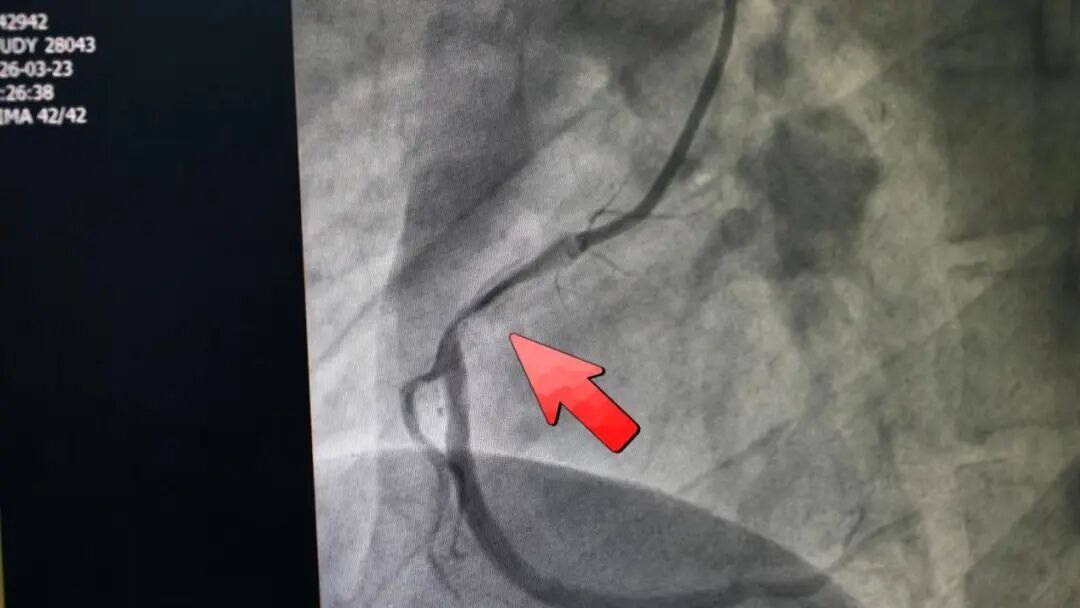

医院立刻开通绿色通道,为陈先生进行手术。“一做造影发现,他三根血管都有问题——右冠状动脉一根,左冠状动脉两根,均存在95%以上的狭窄。”许向东说,“我们及时把左边两根血管疏通。做完手术,他自己才意识到问题的严重性。”